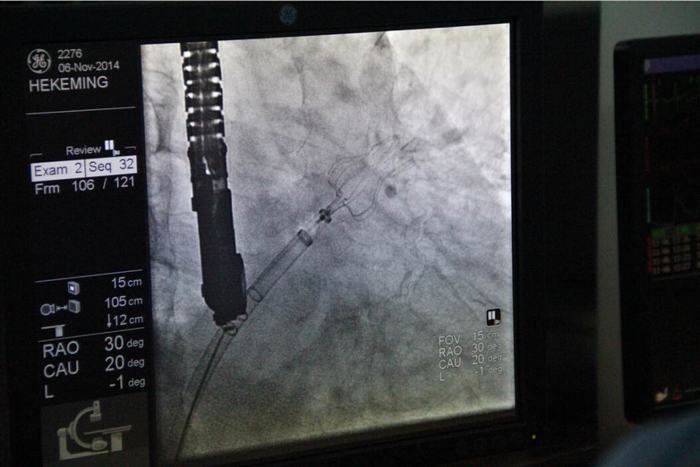

2014年11月6日在我院董事會、院領(lǐng)導(dǎo)及心血管病醫(yī)院各級領(lǐng)導(dǎo)的大力支持下,由德籍華人李教授及兩名美國專家的協(xié)助,心血管病醫(yī)院張玉順院長親自手術(shù),在心臟導(dǎo)管室、外科手術(shù)室及B超室醫(yī)護(hù)人員的全力配合下,經(jīng)過一小時(shí)緊張而有序的工作,順利完成了西北地區(qū)首例“左心耳封堵術(shù)”。此手術(shù)創(chuàng)傷小,痛苦少,恢復(fù)快,預(yù)后好。為目前根治房顫導(dǎo)致中風(fēng)最先進(jìn)及可靠的方法,避免了長期服藥的副作用,減輕了患者的經(jīng)濟(jì)負(fù)擔(dān)。該項(xiàng)技術(shù)國際領(lǐng)先,國內(nèi)剛剛引進(jìn)。此手術(shù)的順利開展預(yù)示著我院醫(yī)療診治及介入手術(shù)水平已跨入國內(nèi)先進(jìn)行列,與國際接軌,填補(bǔ)了西北地區(qū)空白,為廣大患者帶來福音。